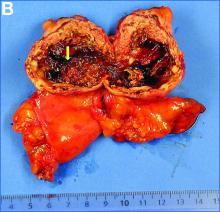

Histologically (Figure C), the fibrous wall contained many large vessels and a small cellular area (star). This area consisted of small nests of moderate-sized monotonous clear cells with normochromatic ovoid nuclei. There was no nuclear atypia and no mitosis. The tumor exhibited an elaborate network of small capillaries. Tumor cells expressed the melanocytic marker HMB45 and smooth muscular actin.